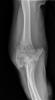

Fractura impactada de húmero .